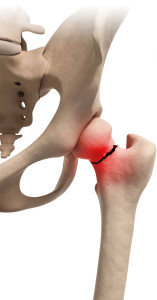

La frattura del collo del femore è quella più frequente. E’ un problema che si aggrava con l’avanzare dell’età a causa di due ragioni in particolare:

- • la diminuzione della quantità di tessuto osseo;

- • la fisiologica perdita di massa muscolare dovuta al passare degli anni.

Le fratture del collo del femore aumentano notevolmente nelle persone al di sopra dei 70 anni e possono essere causate anche da traumi lievi, come una semplice caduta.

Il rischio invalidante di questo tipo di frattura aumenta se l’intervento chirurgico, detto di riduzione, non viene fatto entro le 24/48 ore dall’evento.

Diversi sono i trattamenti chirurgici possibili dopo una frattura:

- PROTESI D’ANCA, nella maggior parte dei casi parziale;

- OSTEOSINTESI: ovvero l’inserzione chirurgica di viti, chiodi o placche per la stabilizzazione della frattura.

Occorrono dai tre ai sei mesi affinché l’osso si rimargini del tutto e per ottenere il massimo recupero della massa muscolare persa a seguito dell’intervento. In questa fase la riabilitazione svolge un ruolo essenziale.